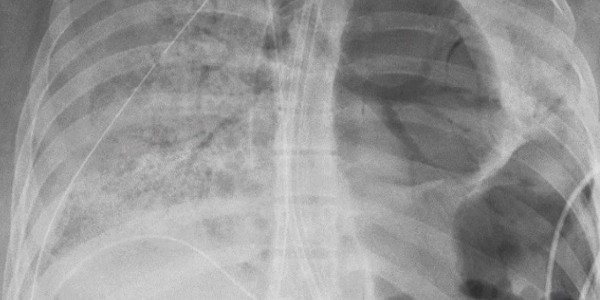

El procedimiento de 10 horas fue desafiante porque el virus había dejado sus pulmones llenos de agujeros y casi se fusionó con la pared torácica, dijo el doctor Ankit Bharat, quien realizó la operación.